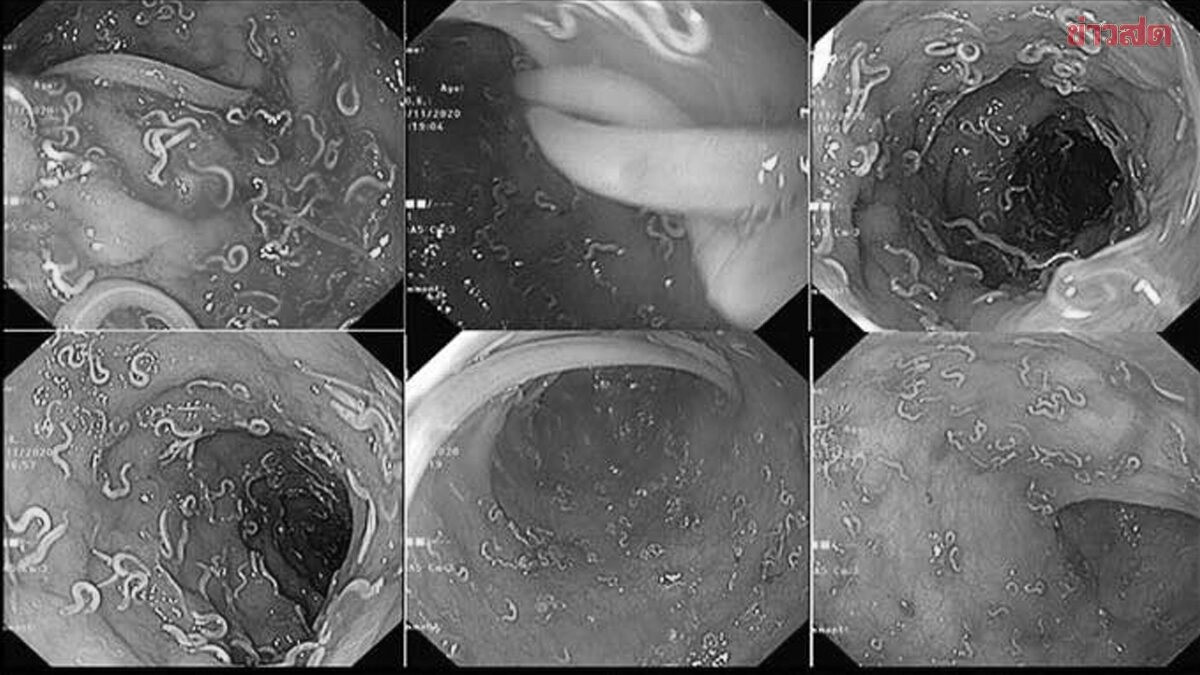

Sau khi điều trị, bệnh nhân được nội soi đại tràng sigma và phát hiện một số lượng lớn giun tóc ký sinh trong niêm mạc trực tràng và đại tràng. Niêm mạc ruột bị đỏ và viêm đặc trưng, được mô tả là "trực tràng bánh dừa" - một dấu hiệu điển hình của nhiễm giun tóc nặng.

Kết quả sinh thiết xác nhận nhiễm trùng Trichuris trichiura, do đó chẩn đoán được đưa ra là hội chứng kiết lỵ Trichuris.